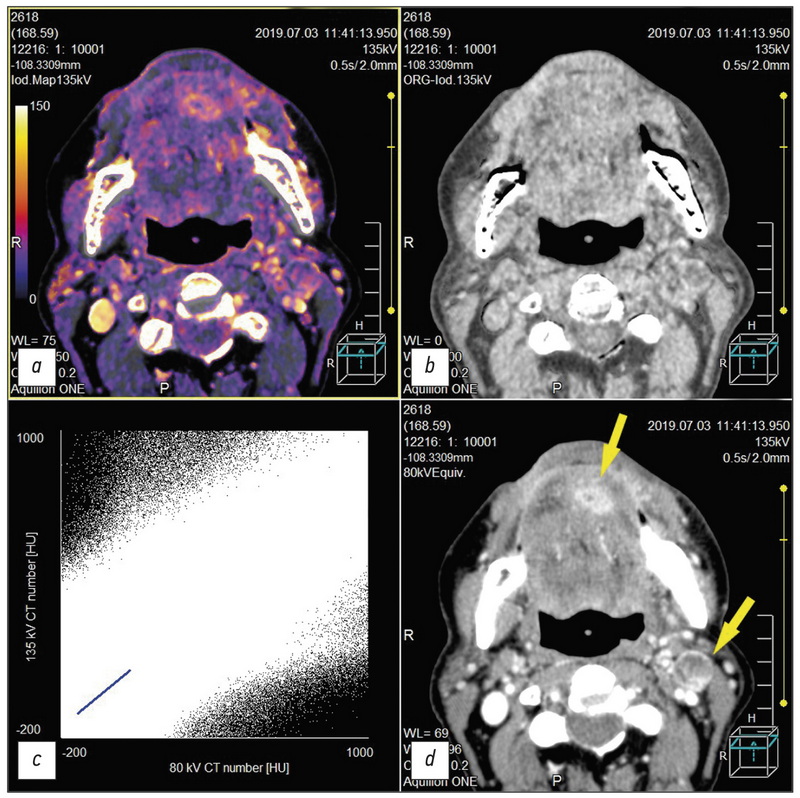

Dual-energy computed tomography for head and neck cancer

This study reviewed the head and neck cancer diagnosis publications using dual-energy computed tomography (DECT). The qualitative and quantitative analysis of the data was DECT obtained using intravenous contrast enhancement for localized tumors, which shows the importance of constructing iodine maps for obtaining additional diagnostic information. Including the article is described aspects of improving visualization of the oropharyngeal region against the background of artifacts from dental implants. Several research articles highlight the current state of the issue and the role of post-processing of “raw data” DECT, obtaining a range of monochromatic images of a tumor and other pathological changes in the head and neck region in the article. Several learned treatises were also reflected. DECT with intravenous contrast enhancement and routine computed tomography to reduce radiation exposure to patients were compared particularly due to the possibility of obtaining virtual native diagnostic images from a contrasting series of DECT volumes during post-processing. In addition, this review also includes references to works that highlight the development of DECT as the method. Finally, the physical principles underlying DECT and the prospects for the development of the method are briefly represented.